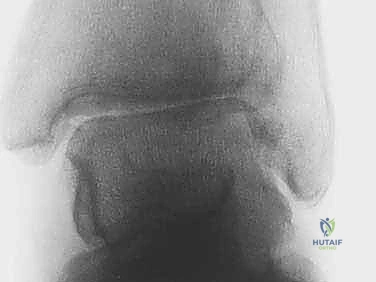

عملية دمج أو تثبيت الكاحل (Arthrodesis) تهدف إلى إزالة الأسطح الغضروفية التالفة بالكامل، ثم وضع عظمة الظنبوب وعظمة الكعب في وضعية تشريحية صحيحة، وتثبيتهما معاً باستخدام براغي أو صفائح معدنية. بمرور الوقت (عادة 8 إلى 12 أسبوعاً)، ينمو عظم جديد بين العظمتين، ليلتحما وتصبحا عظمة واحدة صلبة. بمجرد توقف الحركة في هذا المفصل التالف، يتوقف الألم تماماً.

| معدل التئام العظام (Fusion Rate) | جيد (حوالي 80-85%). | ممتاز (يتجاوز 90-95%) بسبب الحفاظ على التروية الدموية الحيوية للعظام. |